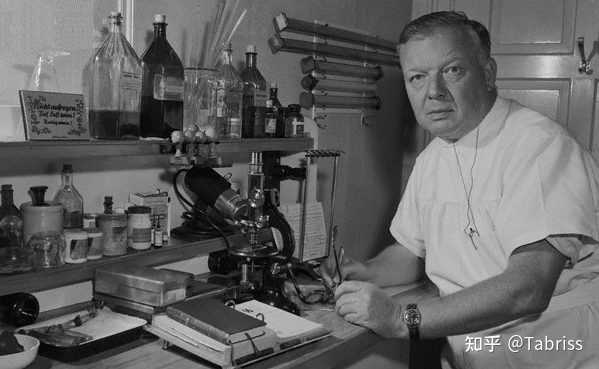

维尔纳・福斯曼(Werner Forssmann) 这种干预的能力来源于什么呢?那就要提到介入医学史上绕不开的传奇人物――维尔纳・福斯曼(Werner Forssmann)。他的故事,即便今天再次在各类学术会议上提起,依然会让所有介入医生心潮澎湃,甚至感到一丝后怕。 那是在遥远的1929年,当时人们普遍认为,任何东西触碰到跳动的心脏都会引发致命的颤动。心脏,是绝对的“禁区”。但福斯曼,这位年仅25岁的德国外科实习医生,却萌生了一个大胆到近乎疯狂的想法:他相信,可以通过一根导管,从外周血管安全地进入心脏内部,进行诊断和治疗。 在遭到上级明确禁止后,他决定用自己做实验。他谎称要在一个女护士身上做,说服她帮忙准备器械,但在最后一刻,他把这位勇敢的护士绑在了手术台上,然后将经过麻醉的自己手臂上的静脉切开。他把一根本用于泌尿科的导尿管,从自己手臂的静脉送入,一路摸索着,将它推进了自己跳动的心脏――右心房。为了证明这一点,他甚至镇定地夹着导管走到了楼下的放射科,拍下了一张足以载入史册的X光片。 他用自己的心跳和生命作为赌注,推开了一扇通往全新世界的大门。 这次石破天惊的自我实验,证明了心导管技术的可行性和安全性,为后来的心脏造影、冠脉介入治疗(比如我们熟知的支架手术)乃至我们整个介入学科的发展,奠定了最重要的一块基石。 然而,在当时,他的惊世之举换来的不是赞誉,而是上级的震怒和同行的嘲笑,他因此被医院开除,一度被迫中断了心血管研究的生涯。直到多年后,两位美国医生在他的基础上将心导管技术发扬光大,福斯曼的开创性贡献才被重新认识。1956年,他们三人共同获得了诺贝尔生理学或医学奖。 最后,西医的进步,还深刻地改变了我们对“生命长度”和“生命质量”的认知。曾几何些时,人均寿命不过三四十岁,一场肺炎、一次阑尾炎就可能夺走一个人的生命。而现在,因为疫苗,天花被彻底消灭;因为抗生素,细菌感染不再是绝症;因为胰岛素,糖尿病患者可以有尊严地长期生活。对于我们肿瘤科医生而言,很多时候我们追求的不再是“治愈”,而是“带瘤生存”。西医带来的,不仅仅是治愈的奇迹,更是一种与疾病共存的智慧和勇气。 它把许多疾病从“急性死亡事件”变成了可以管理的“慢性病”,让生命的终点不再那么猝不及防,也让过程中的痛苦得以减轻。 当然,西医绝非万能。它有时显得冰冷、昂贵,它在攻克癌症、阿尔兹海默症等顽疾的道路上依然步履维艰。作为一名医生,我每天也都在面对它的局限性,感受着技术天花板带来的无力感。但它最重要的是,我们可以承认自己的局限,并驱动着全世界很多聪明人,日以继夜地去突破这些局限。 所以,如果问我西医给人类带来了什么?我想,它带来的是面对疾病时,我们作为“人”的主动权。它让我们从祈求神明、听天由命,到能够拿起手术刀、导管、显微镜、基因测序仪,去观察它、理解它、对抗它,甚至在某些时候,与它和解。它给了我们延长生命的机会,更给了我们维护生命尊严的工具。 那么,在你或你家人的经历中,现代医学给你留下最深刻的印象是什么?是某个瞬间,某项技术,还是某位医生的一句话?欢迎在评论区聊聊。 送礼物 还没有人送礼物,鼓励一下作者吧 |